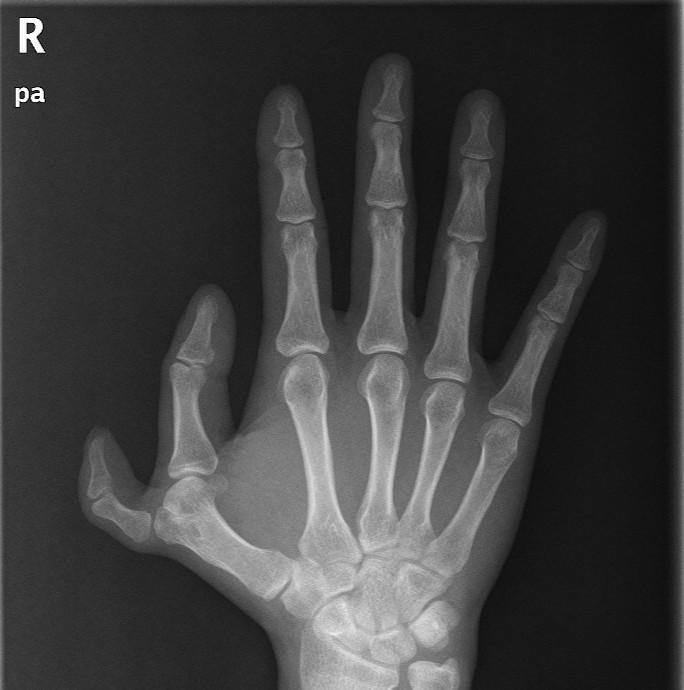

多指一例!

图片尺寸2432x3648